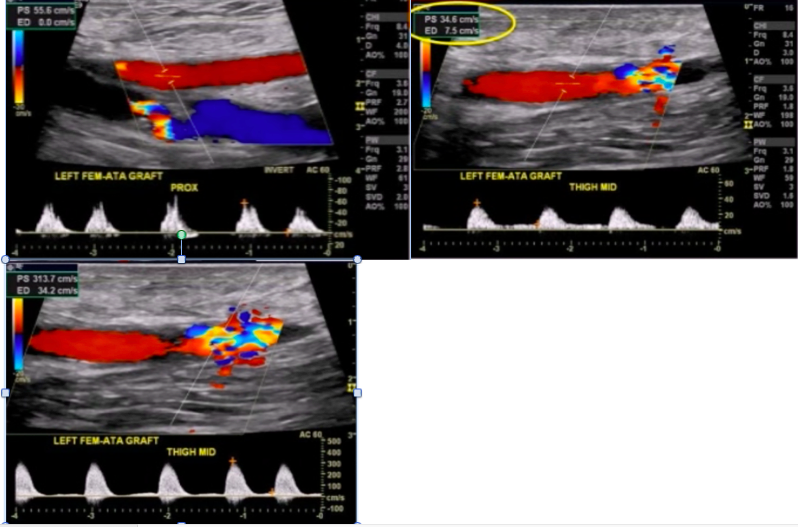

Pt undergoes LE arterial DUS. Interrogation of femoral-ATA graft is shown below.

Most important finding to report?

50-99% gypass graft stenosis

note the PSV ratio ~10, monophasic waveform proximal to lesion, and turbulent color flow near lesion